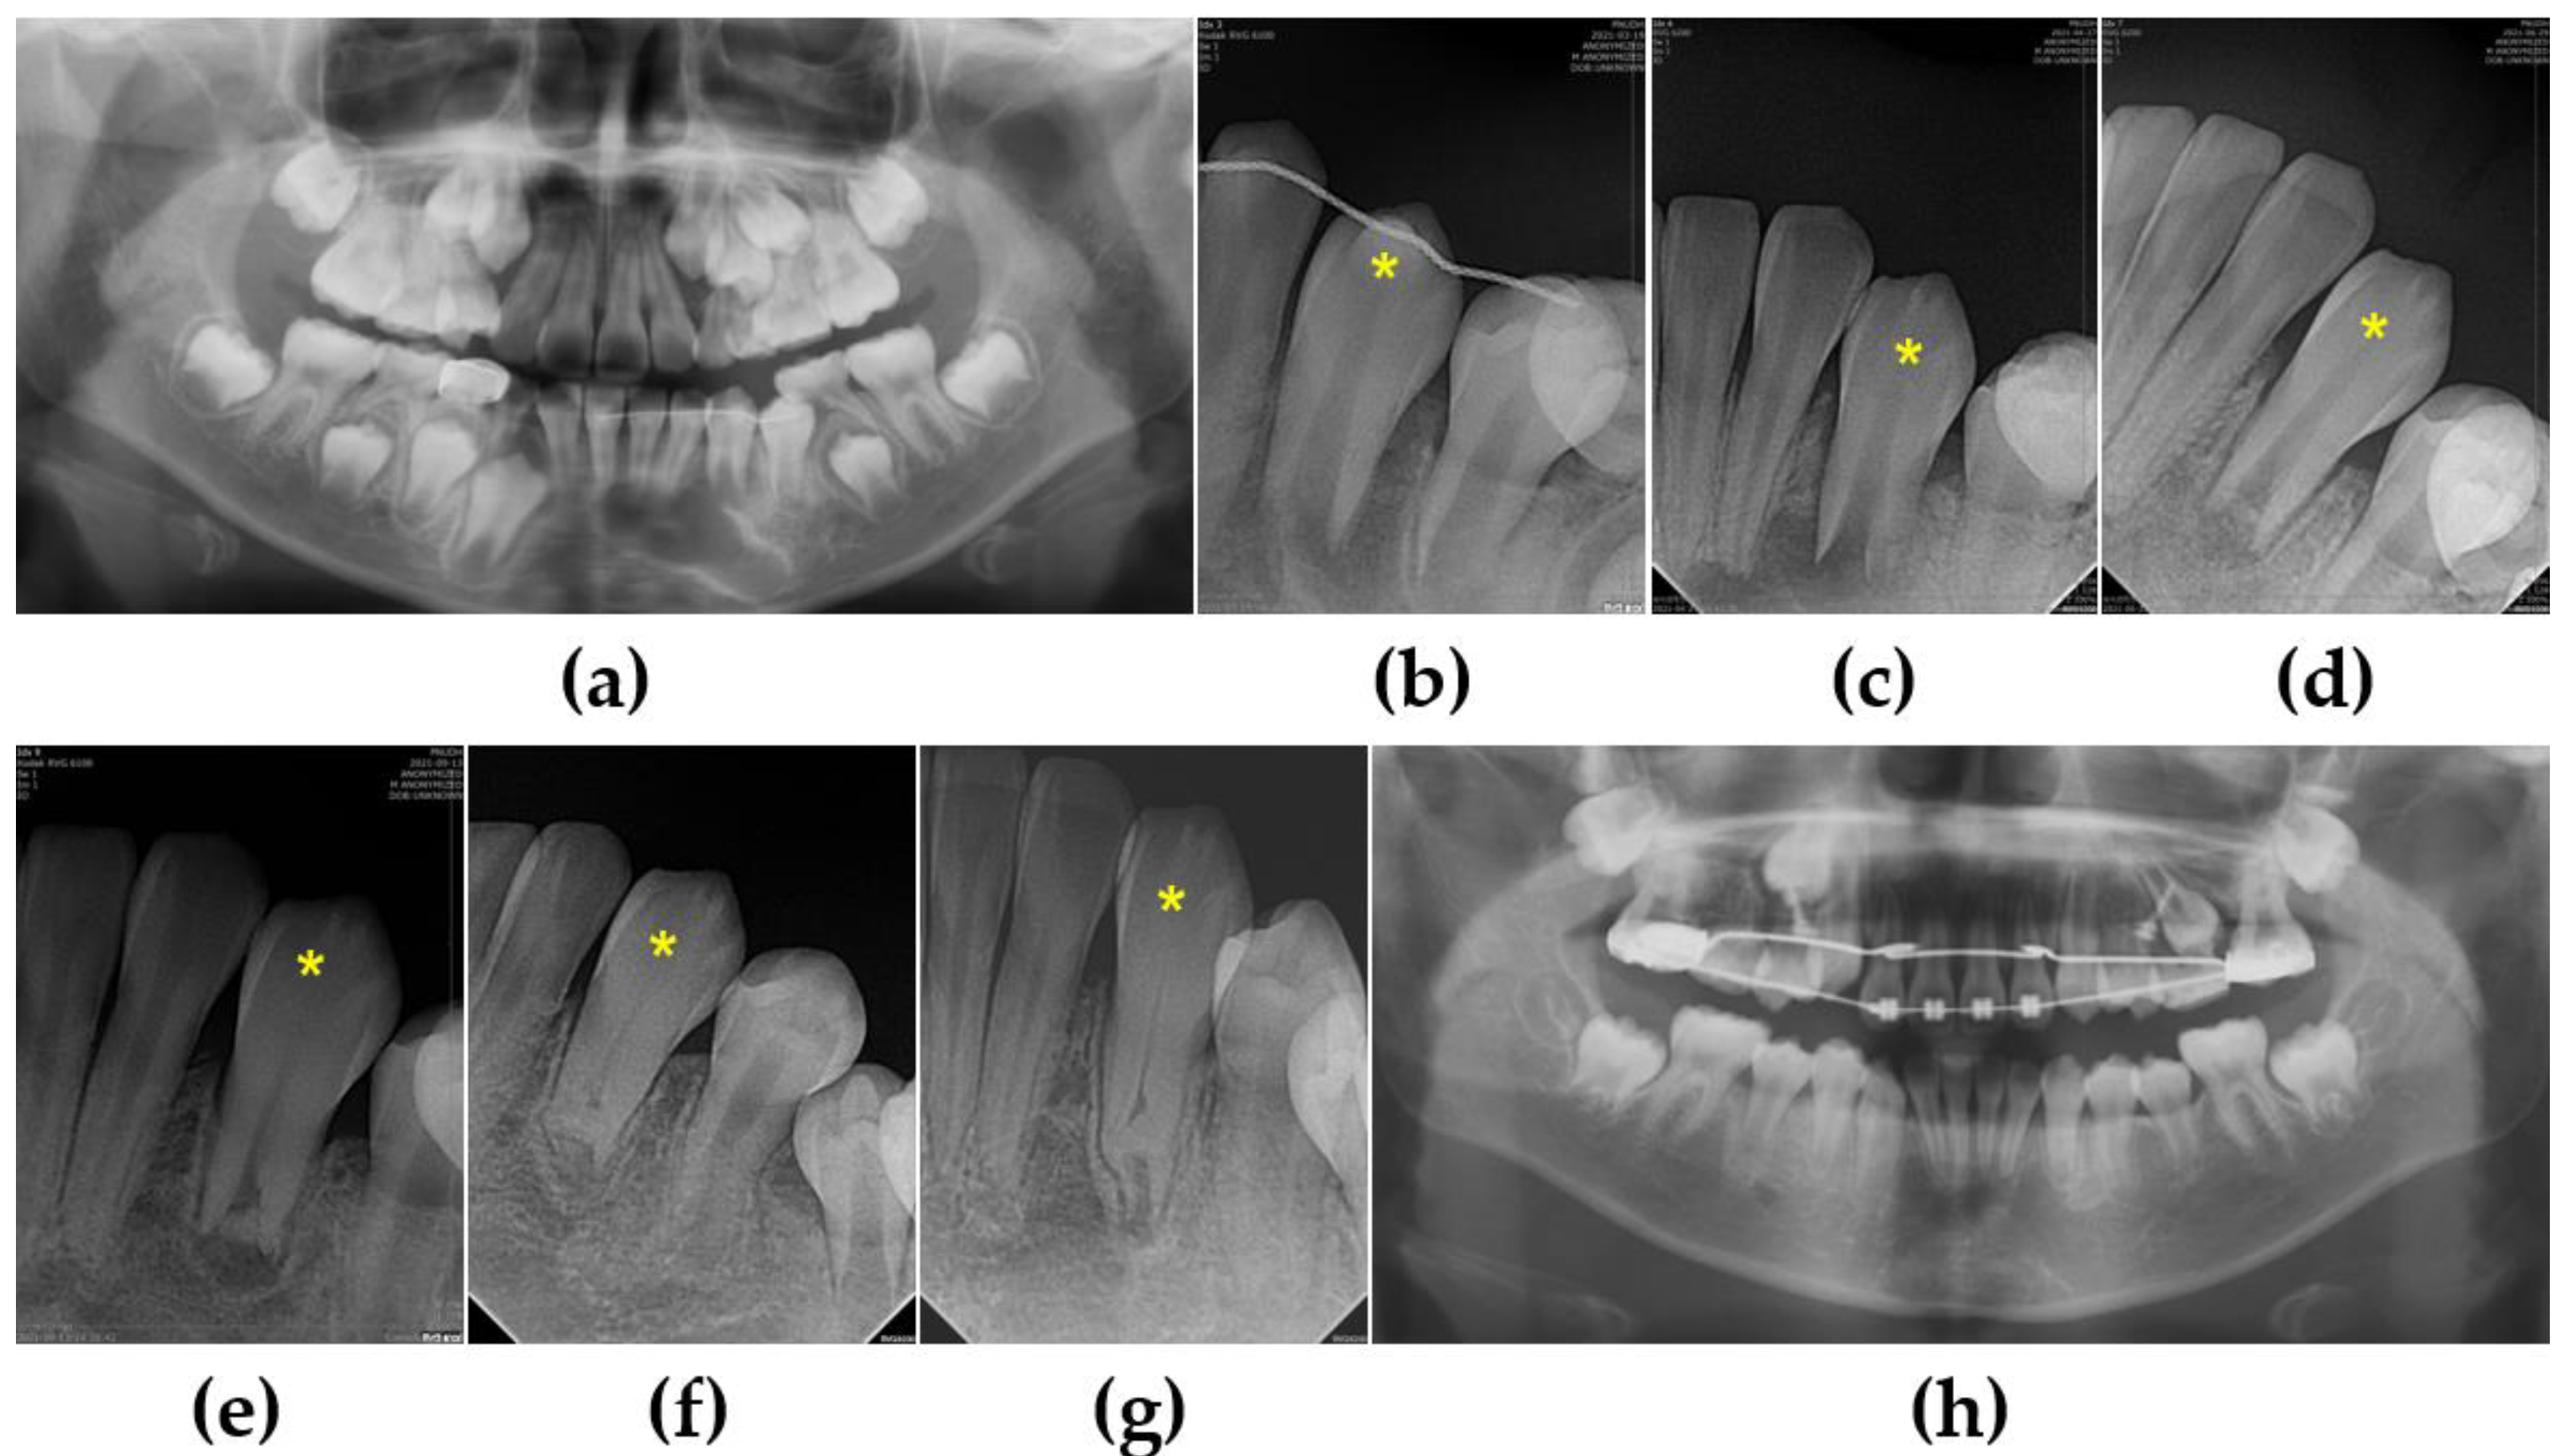

3.2. Case 2